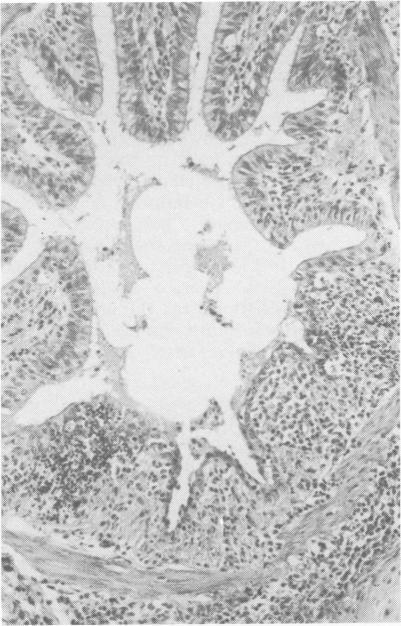

Seven experiments with four calves each were conducted in which the calves spent at least four days of adaptation in an environmental chamber and then were subjected to climatic stress in the form of a number of constant ambient temperature and humidity combinations. On the second day of climatic stress the calves were individually exposed to measured numbers of infectious units of bovine herpesvirus 1 (BHV1, virus of infectious bovine rhinotrachetis) in aerosol. The calves were killed seven or eight days later. Mycoplasma were found in some nasal swabs and in one lung. Certain bacteria but no Pasteurella were often isolated from the lungs. Bovine herpesvirus 1 was isolated from chamber air and from most postinoculation nasal swabs, tracheas and lungs. The number of macro- and microscopic lesions did not appear to be influenced by the climatic conditions of the experiments. The histopathological changes in epithelium at all levels of the respiratory tract were described in detail.

进行了七项实验,每项实验有四头小牛。小牛在环境舱中至少度过四天的适应期,然后经受多种恒定环境温度和湿度组合形式的气候应激。在气候应激的第二天,小牛被单独暴露于经测量数量的牛疱疹病毒1(BHV1,传染性牛鼻气管炎病毒)气溶胶感染单位中。小牛在七或八天后被宰杀。在一些鼻拭子和一个肺中发现了支原体。肺部经常分离出某些细菌,但未分离到巴氏杆菌。从舱内空气以及大多数接种后鼻拭子、气管和肺中分离出了牛疱疹病毒1。大体和微观病变的数量似乎不受实验气候条件的影响。详细描述了呼吸道各级上皮的组织病理学变化。